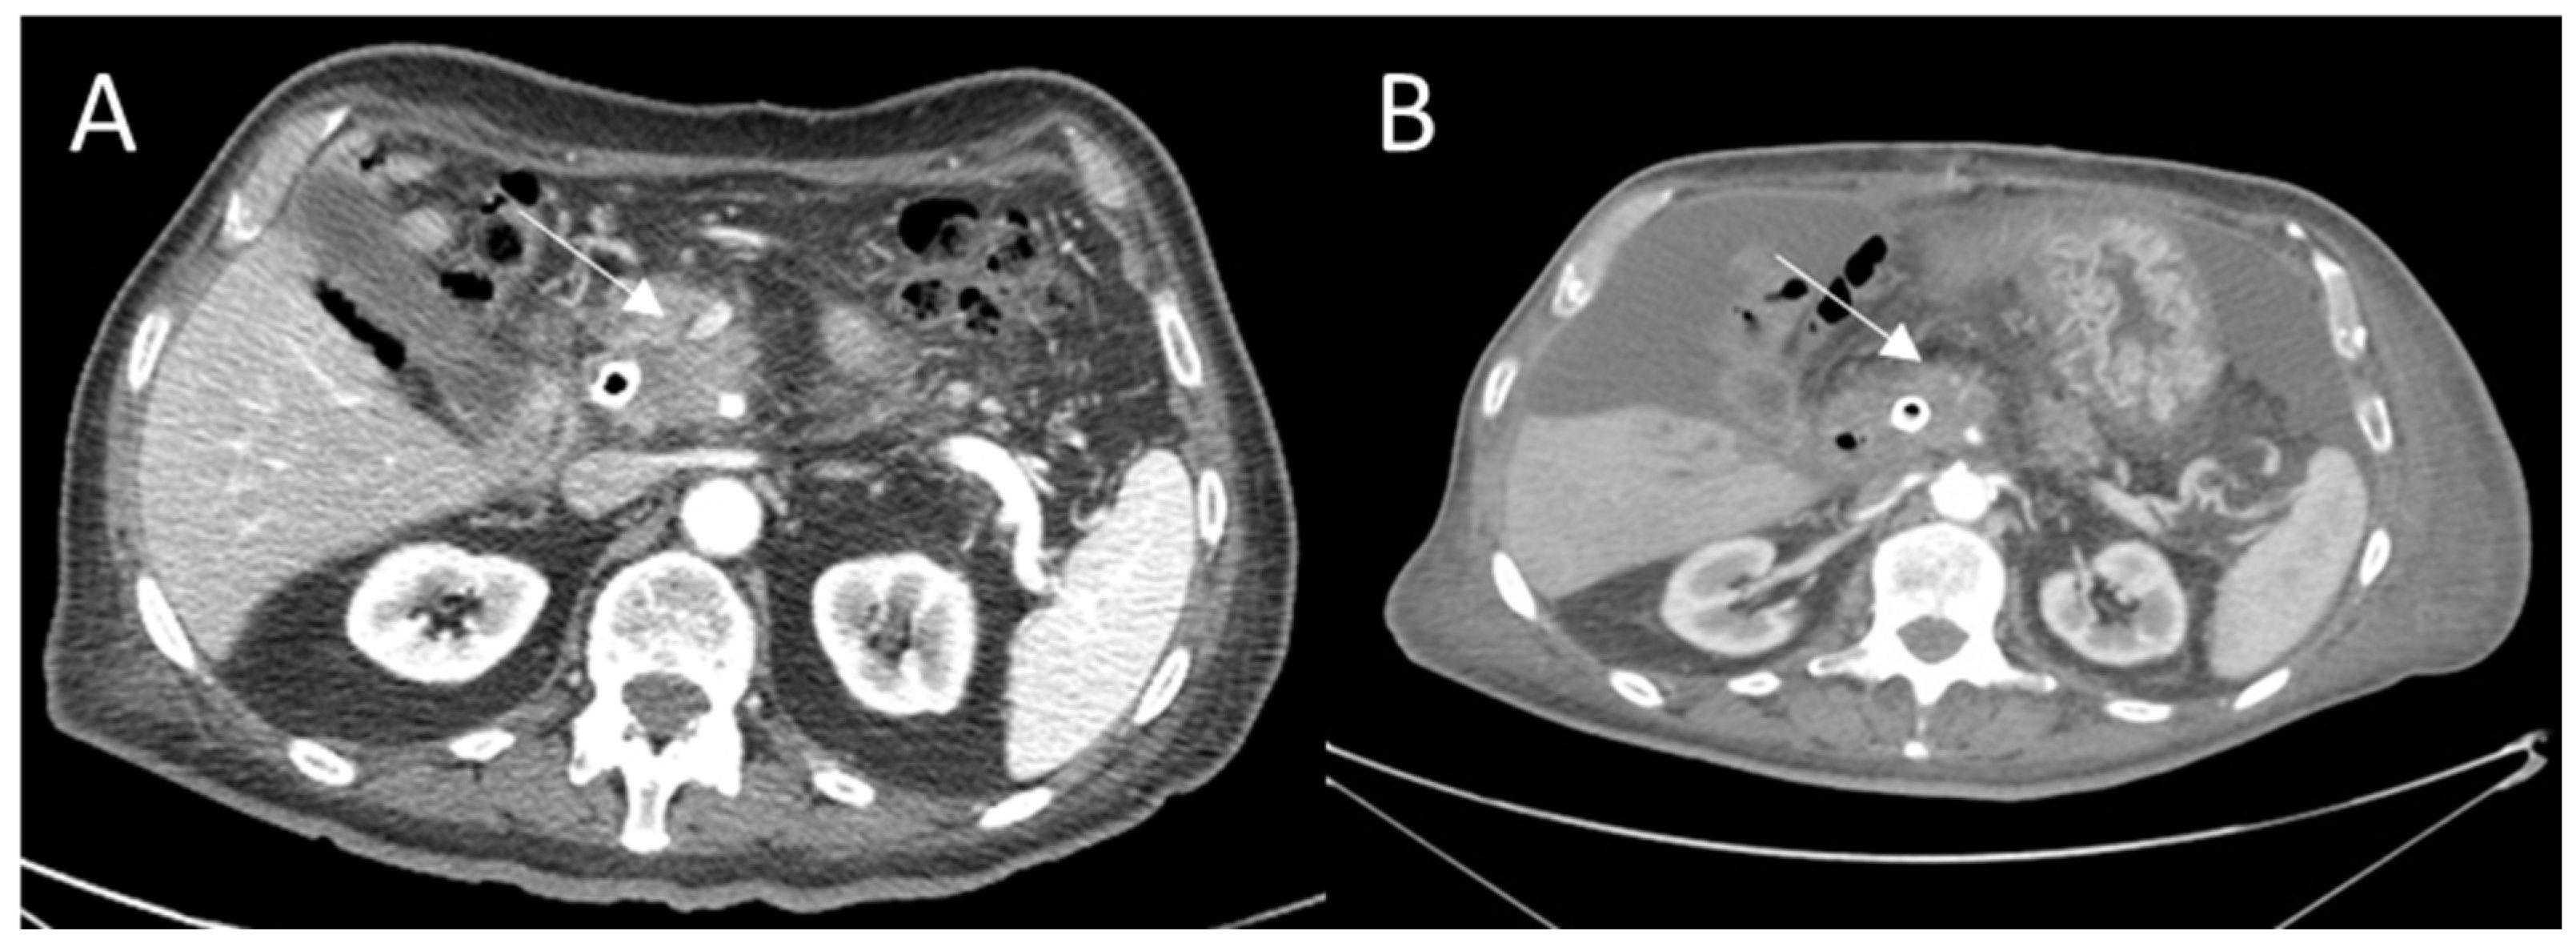

| Computed Tomography | No significant difference was observed after ECT in CT equilibrium-phase of contrast study. | Immediately after IRE, intralesional and periablational gas pockets | One week after RFA, the ablation zone was visible as partially sharply defined and heterogeneous area | [22,26,78,79,84] | |

| Reduction of HU density was observed on treated area. | Post-IRE the ablation zones were primarily hypodense in the arterial phase after 6 weeks and 3 and 6 months. In the portal venous phase, the ablated areas were slightly hypodense immediately post-IRE; at 6 weeks and 3- and 6-month follow-up | hypointense area and inhomogeneous enhancement are observed as result of the treatment. | |||